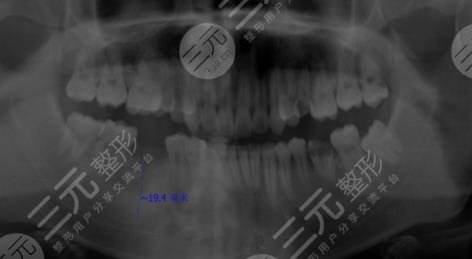

在朋友的推荐下,我来到了茂名致美口腔医院进行检查,医生说我的牙齿已经拖得太久了,神经都要坏死了,只能够通过种植牙的技术来进行改善了,虽然价格比较昂贵,但是为了不让自己受这样的折磨,只能接受了。现在已经是尽兴玩种植牙手术后的三个月了,大家可以看到我的牙齿恢复的还是比较好的,而且看起来比之前更加的整洁和自然了,现在未有更加的爱护自己的牙齿了呢。